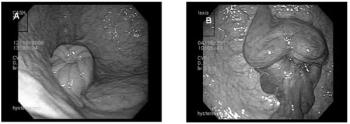

Endoscopic examination of the mare's uterus is primarily used as tool to aid in the diagnosis of unusual conditions, such as intractable infections, tumors, abscesses, foreign bodies, adhesions, and congenital abnormalities.